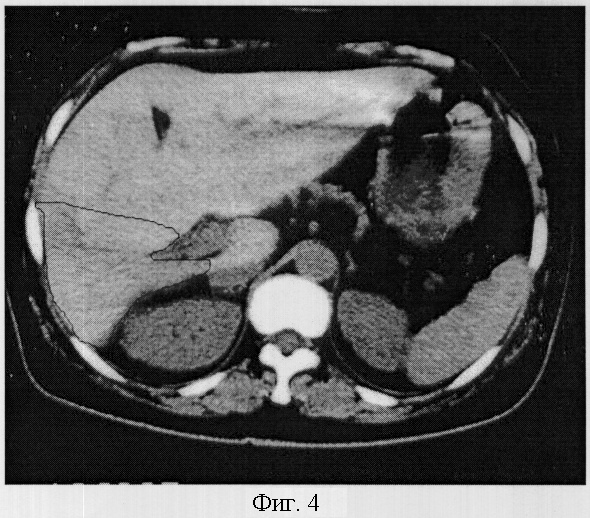

Пример 4. Гипоплазия 2 степени.

Больная Головач Л.И. 54 лет, направлена компьютерно-томографическое обследование с подозрением на опухоль печени. При исследовании отмечается некоторое увеличение объема печени, преимущественно за счет левой доли. Объем печени составил 1584,3 см3, объем правой доли – 295,8 см3. Печень расположена нормопетально, поверхность печени гладкая, контур в области расположения 6 и 7 сегментов деформирован. Структура паренхимы однородная, плотность 63 HU. Изменение объема правой доли обусловлено уменьшением объема 5-8 сегментов, объем которых варьировал от 69,3 до 71,6 см3, а коэффициент К=0,29 и 0,28, что соответствовало гипоплазии 2 степени. Диаметр сегментарных ветвей правой доли был уменьшен неравномерно и варьировал от 0,51 в восьмом сегменте до 0,49 в пятом (фиг.4).